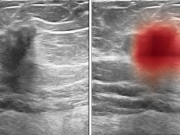

AI Could Improve Accuracy of Breast Ultrasound Diagnosis

Artificial intelligence system achieved higher AUROC than average of 10 board-certified breast radiologists